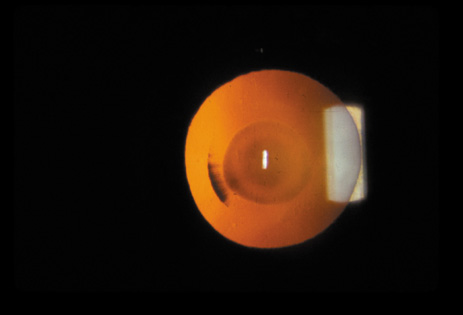

Nuclear cataracts tend to progress slowly. The refractive index of the lens changes as the nucleus progressively hardens, which usually results in increasing myopia.20,21 In some patients this is accompanied by optical distortion, especially of distant images, while near vision remains unaffected. A nuclear cataract is best seen with the narrow-beam direct illumination employed by the slit-lamp, which reveals the color and generalized haze or opalescence of the nucleus. In the early stages, the two halves (cotyledons) of the embryonic nucleus remain visible (Fig. 3). Later the entire nucleus appears as a homogeneous mass in contrast to the cortex (Fig. 4). Retroillumination may show the “oil droplet” effect (Fig. 5). Sometimes one may notice crystals in the lens nucleus (known as a Christmas tree cataract; Fig. 6A and B).

Fig. 4. Advanced nuclear cataract. Note the homogeneous nuclear opacity.